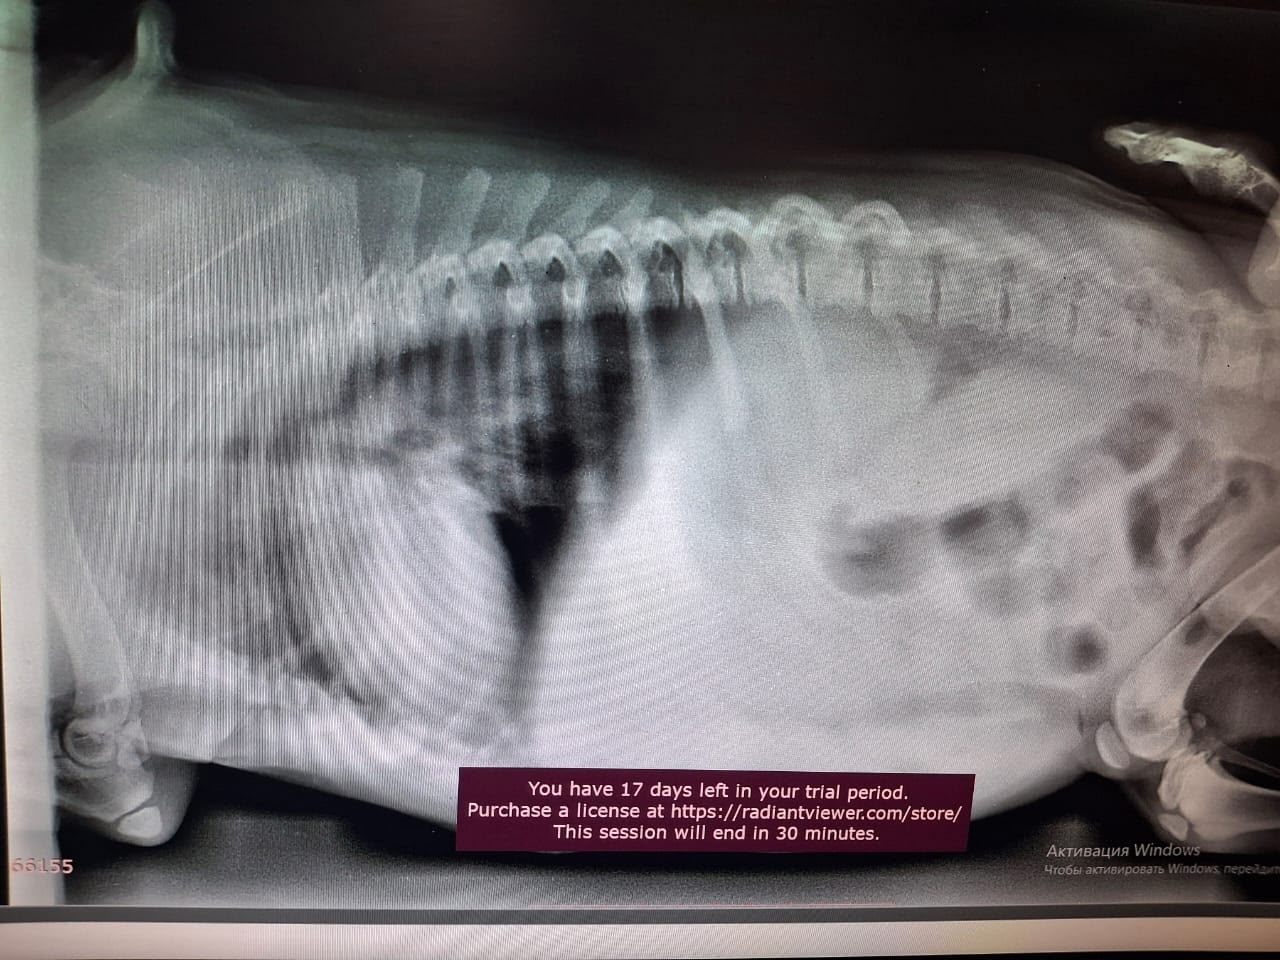

Анонимно. Будьте внимательны, при выборе питомца. Всё о питомнике Ам Стаффордширских терьеров. Вот таких больных животных там продают за не маленькие деньги, Екатерина Кудрявцева владелец питомника.